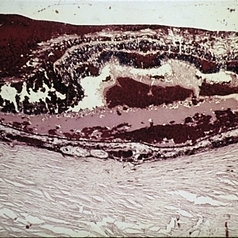

Slide 7-31

Feb 25 2019 by Lancaster Course in Ophthalmology

Keloid of the cornea. The entire cornea has been replaced by thickened, dense scar tissue.

Condition/keywords: cornea, scar